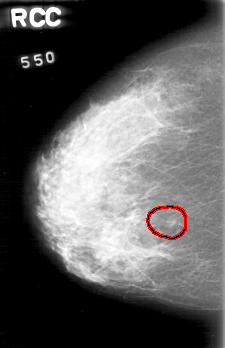

D_4022_1.RIGHT_CC

RIGHT_CC LINES 5206 PIXELS_PER_LINE 3361 BITS_PER_PIXEL 12 RESOLUTION 43.5 OVERLAY

FILE: D_4022_1.RIGHT_CC.OVERLAY

TOTAL_ABNORMALITIES 1

ABNORMALITY 1

LESION_TYPE MASS SHAPE ROUND MARGINS OBSCURED

ASSESSMENT 0

SUBTLETY 5

PATHOLOGY BENIGN

TOTAL_OUTLINES 1

BOUNDARY